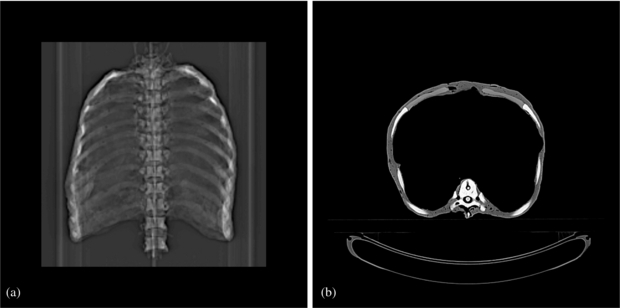

2.5.3. Dosimetry

To allow treatment planning we performed 18 3DCT scans (Somatom Sensation Open—Siemens AG Healthcare, Erlangen, Germany; resolution: 1 × 1 × 1 mm3), one for each motion state every 20º distributed over one thorax motion cycle. (The topogram and one axial slice are shown in figure 2.) The detector head CT was incorporated into the 4DCT phases according to the planned motion using a dedicated CT merging software. Thus, we generated a 4DCT free-of-motion artefact and a higher number of motion states than normally used for standard 4DCT reconstruction. To ensure having the right HU values, we measured the WEPL of material samples using the PTW Peakfinder™ (PTW, Freiburg, Germany) and a carbon beam at Heidelberg Ion-Beam Therapy Center (HIT, Heidelberg, Germany). Then we replaced the HU values with the ones corresponding to the measured WEPL values (Jaekel et al 2001).

Figure 2. CT scan of the thorax. (a) Topogram. (b) Representative axial slice.